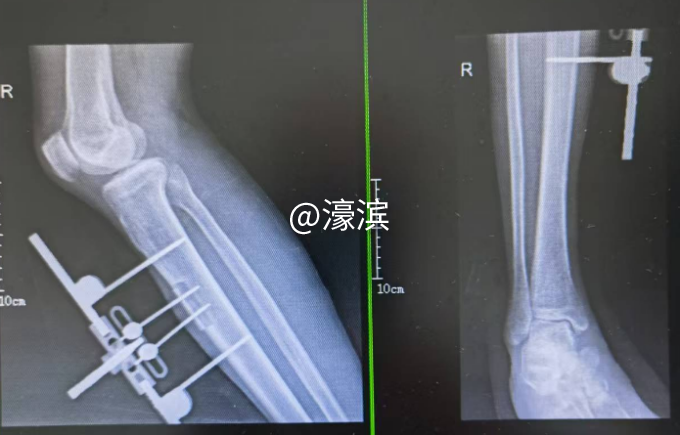

△胫骨搬运术前术后CTA血管对比,血管再生良好

经过胫骨横向搬运及多次清创术,下肢血管再生,右足新鲜肉芽组织生长良好,行游离植皮术,创面完全愈合,功能恢复。 细节铸就奇迹:全程管理护航康复 术后,心电监护仪持续追踪血压、血氧、心率变化,确保患者平稳过渡;通过静脉镇痛泵缓解疼痛,同时每2小时观察伤口敷料渗血、渗液情况,严防早期感染;根据血糖变化,及时调整药物剂量,每日8小时一次调整骨搬运牵引针刻度,确保骨膜张力,重建下肢血运。